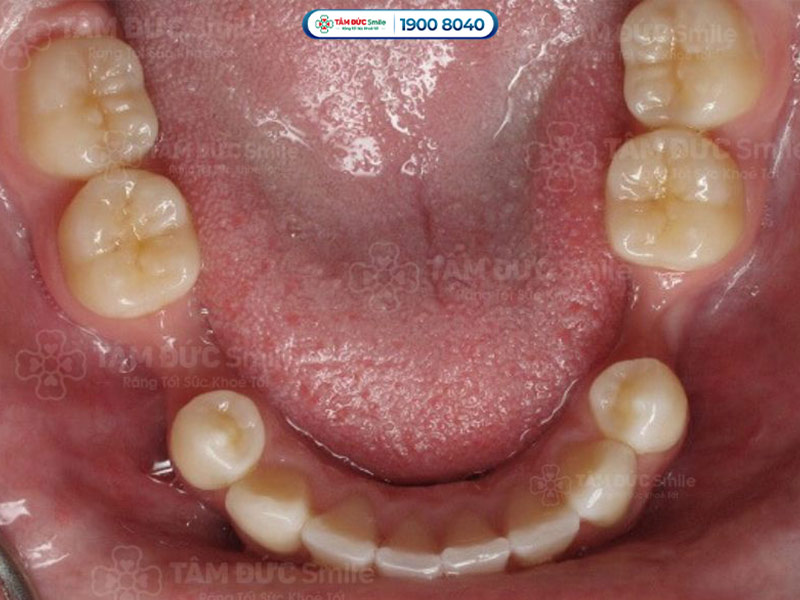

1.2. Mất răng lâu năm làm răng kế cạnh bị xô lệch

Mất răng lâu năm làm cho các răng xung quanh xô dịch do mất điểm tựa vững chắc. Lực nhai không được phân bổ đều mà tập trung vào các răng còn lại. Răng thường có xu hướng nghiêng về khoảng trống để lấp đầy.

Răng khấp khểnh do xô lệch tạo ra kẽ hở giữa hai răng, dẫn tới tình trạng răng thưa. Răng đổ xô dịch kéo dài sẽ làm thay đổi khớp cắn và ảnh hưởng tới khớp thái dương hàm. Vấn đề này có thể làm cho Quý khách cảm thấy đau nhức vùng tai, thái dương và vùng đầu.

Mất răng lâu năm làm cho các răng xung quanh xô dịch do mất điểm tựa vững chắc